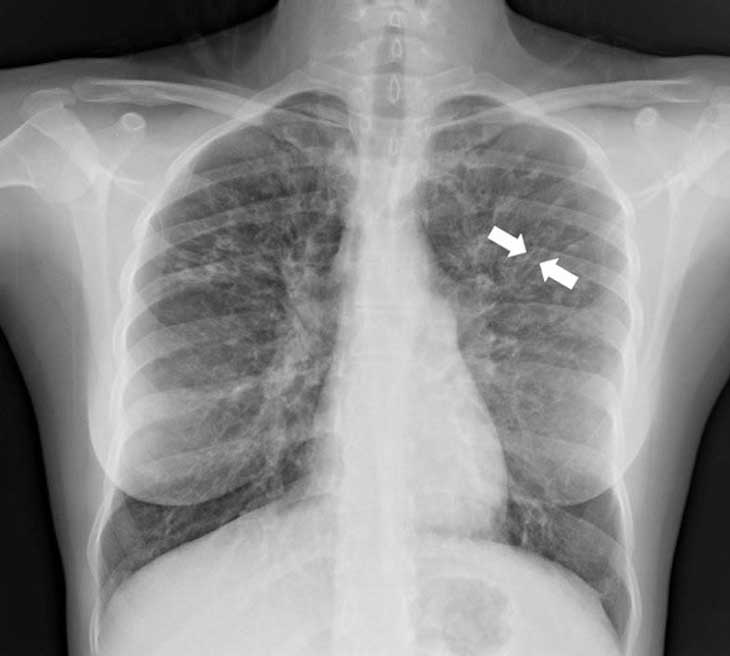

giãn phế quản Hình ảnh chụp X-quang một bệnh nhân giãn phế quản